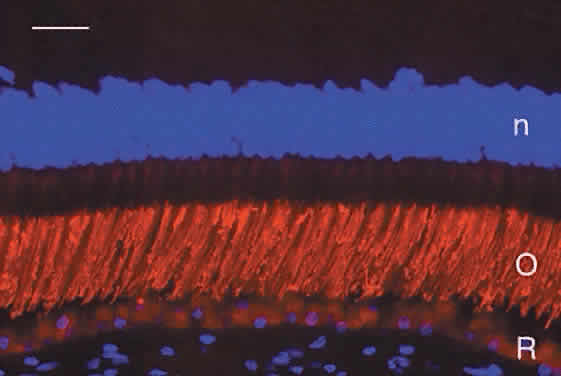

layer of photoreceptor axons and synapses (see Fig. 5B). Humans have a single type of rod with a long, thin outer segment containing the visual pigment, rhodopsin, which absorbs maximally at 500 nm. The cone outer segments are shorter and wider and somewhat conical. Each of the three cone types contains a different cone opsin that absorbs maximally in the red (564 nm; L cones), green (533 nm; M cones), or blue (437 nm; S cones) region of the spectrum. The visual pigments can be demonstrated by immunocytochemistry using antibodies specific for the different proteins. Rod outer segments are strongly labeled with anti-rhodopsin (Fig. 6). The composition of the red cone pigment is so similar to that of the green cone pigment that they cannot be differentiated by immunocytochemistry, but the majority of cone outer segments are labeled with an antibody that recognizes both red- and green-sensitive cones (Fig. 7A). A minority of the cones are blue-sensitive (see Fig. 7B).